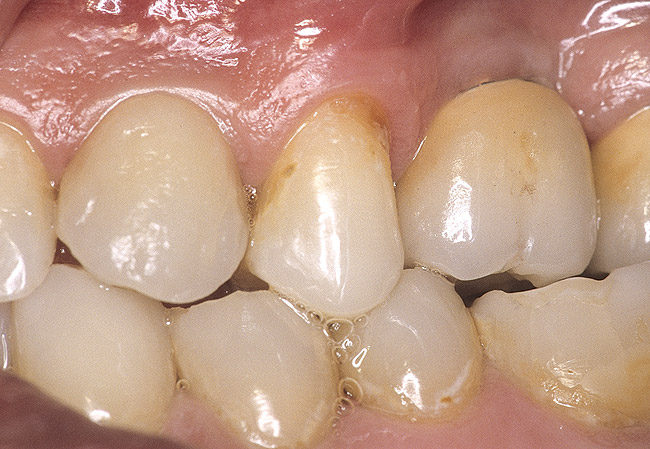

Second-stage surgery was performed after 4 months (Figure 8); healing abutments were placed and the soft tissue was allowed to heal for 5 more weeks. Then, splinted porcelain-fused-metal (PFM) crowns supported by custom gold abutments were delivered (Figure 9 and Figure 10).

Figure 9  Final implant-supported PFM restorations.

Figure 9

Figure 10  Posttreatment radiograph, after cementation of the final restorations.

Figure 10